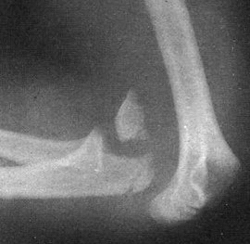

Диагностика вывиха предплечья

В анамнезе — травма. Сустав отёчен и деформирован. На задней поверхности, на расстоянии от плеча, под кожей выступает локтевой отросток. Нарушены треугольник и линия Гютера. Предплечье укорочено. Активные и пассивные движения в локтевом суставе отсутствуют, их попытка вызывает острую боль. Отмечается положительный симптом пружинящего сопротивления.

На рентгенограммах в двух проекциях видно разобщение сочленяющихся поверхностей плеча и предплечья.

Наиболее распространены задние вывихи обеих костей предплечья (до 90% всех вывихов локтевого сустава). Вывихи могут быть полными и неполными; при неполных сохраняется частичное соприкосновение суставных поверхностей.

Вывихи возникают как от прямой, так и от непрямой травмы. Под действием силы предплечье смещается в определенном направлении. Обе кости, связанные кольцевидной связкой и межкостной мембраной, обычно смещаются вместе; вывих одной кости встречается реже. Вывихи могут осложняться отрывом венечного отростка (чаще при задних вывихах), переломами локтевой и лучевой костей, мыщелков и отрывами надмыщелков плечевой кости.

Этот тип вывиха чаще всего происходит при падении на ладонь (непрямая травма) с разогнутой рукой в локтевом суставе. Резкое переразгибание приводит к упиранию локтевого отростка в локтевую ямку, разрыву передней части суставной сумки и смещению нижней части плеча вперед. Предплечье подтягивается кзади из-за сокращения трехглавой мышцы.